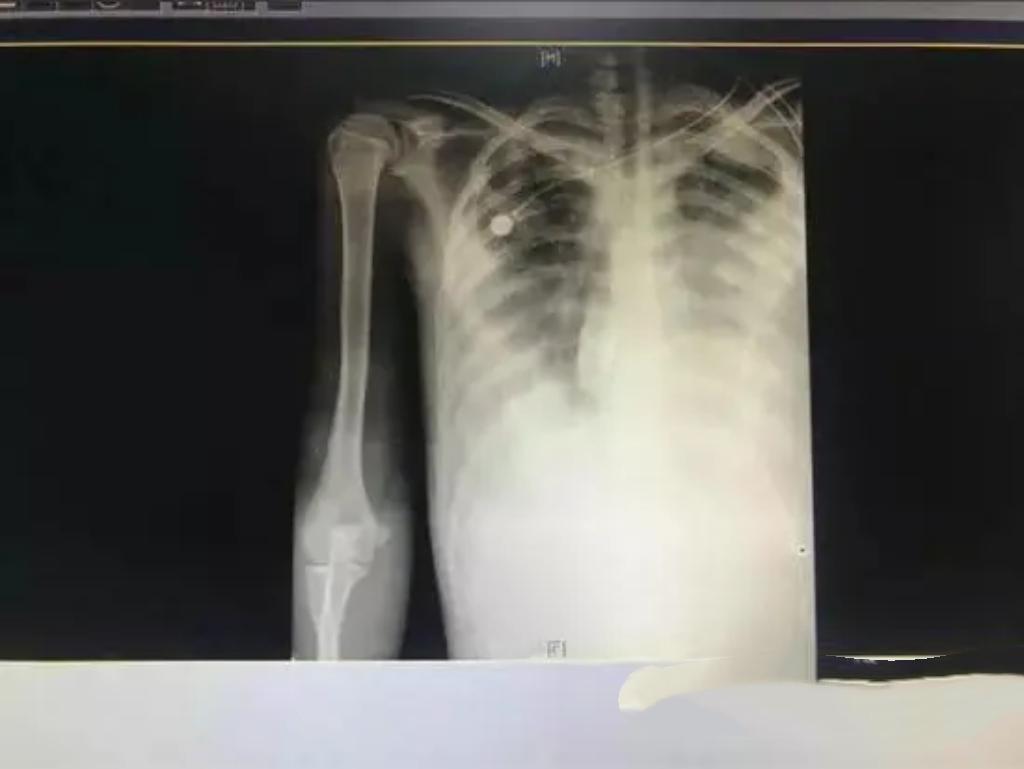

20岁男生小李长期熬夜、饮食不规律,免疫力下降,竟被结核杆菌“盯上”,肺部被“啃”出10多个空洞,咳嗽、发热、咯血等症状频发。所幸及时就医,经规范抗结核治疗,病情逐渐好转。提醒年轻人,务必重视健康,规律作息。